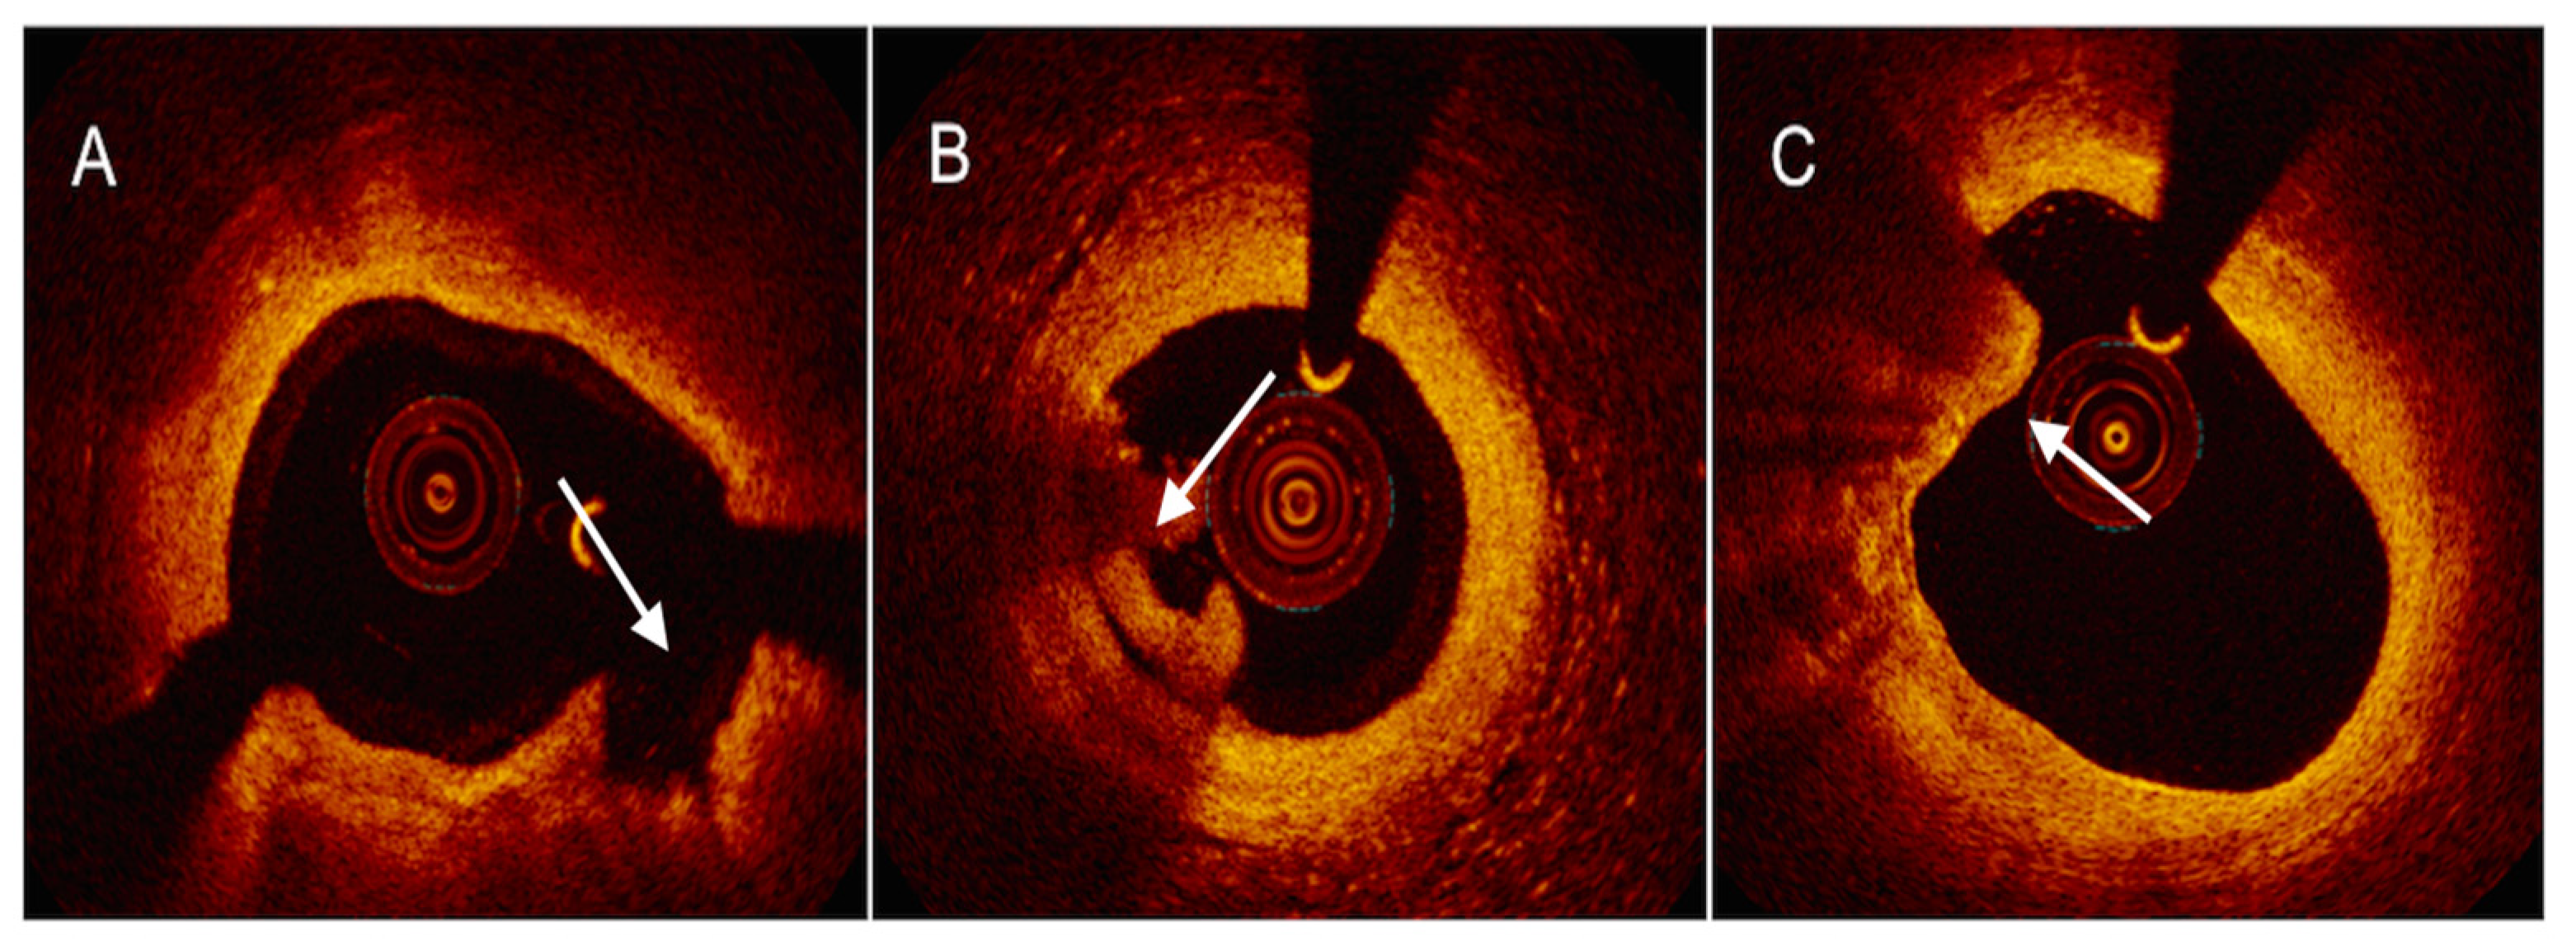

4.2. Optical Coherence Tomography

4.3. Near-Infrared Reflectance Spectroscopy